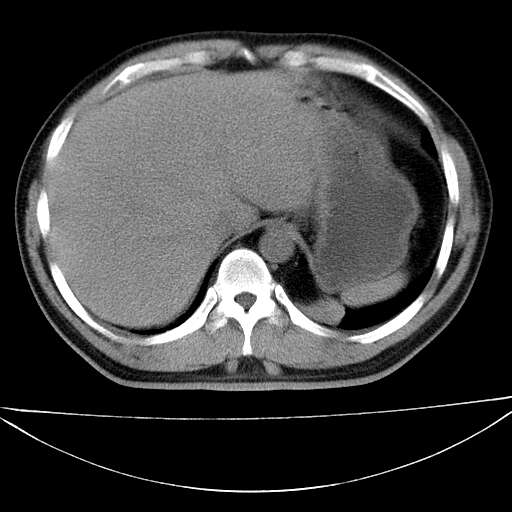

标题: CT21921:腹膜后腔肿物。患者男39Y。体检。增强扫描时间欠准

左侧膈肌脚外缘见一结节样软组织影,密度较均匀,与胸膜关系稍密切,增强轻度强化;考虑来自胸膜良性病变(胸膜纤维瘤可能)。建议加扫胸部ct检查。

2、左下膈肌脚外缘结节状病变,与胸膜交界面呈锐角,胸膜下脂肪线可见,定位于肺内,考虑支气管囊肿或肺隔离征可能性大。

1)考虑左肺下叶后基底段(或左下胸后壁胸膜)软组织团块,性质待定;建议行进一步检查。2)左肾结石。

左膈肌连续性中断,左侧膈疝可能性大.

左膈肌角后腹膜腔见肿物影,其内见脂肪密度灶及软组织密度灶,强化不明显。病灶大部在后腹膜内。考虑异位嗜铬细胞瘤或脂肪肉瘤、畸胎瘤

左下肺隔离症,可见从胸主动脉发出异常血管供应